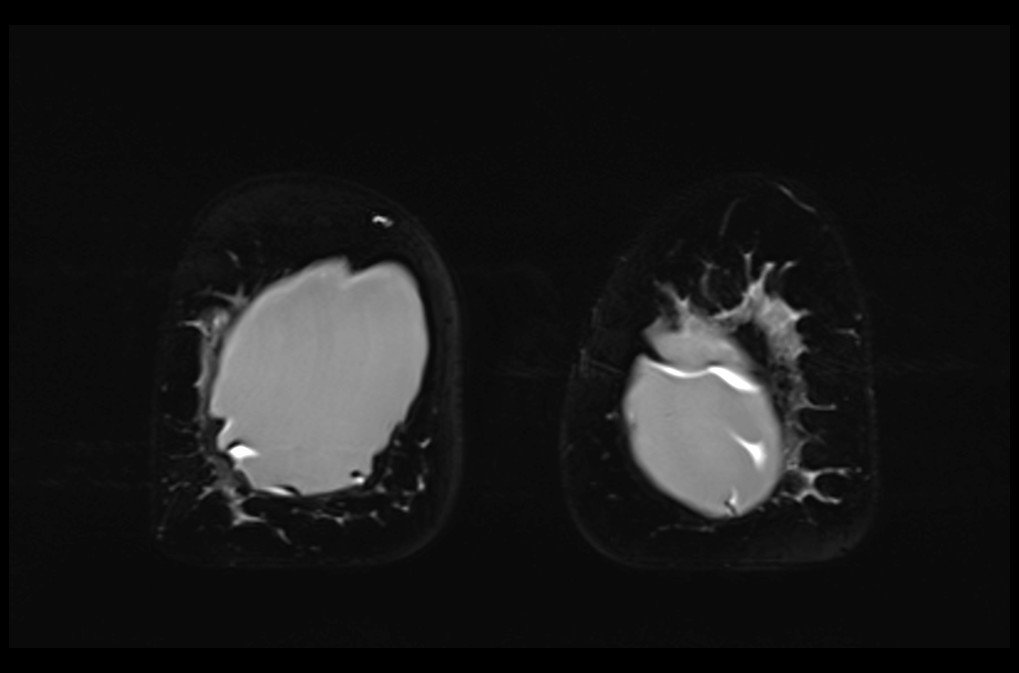

MRI breast implant stir coronal images 4 - MRI